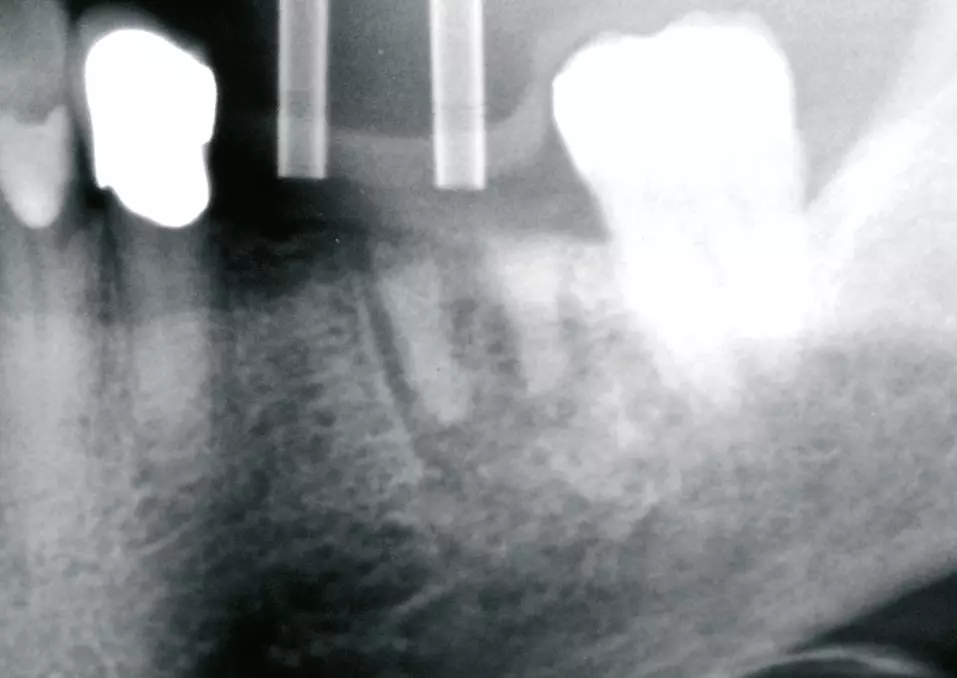

Vor dem abschließenden spannungsfreien und speicheldichten Wundverschluss (Abb. 10) erfolgte die Abdeckung der Implantate und des Knochenaufbaus mit einer Kollagen- (Geistlich Bio-Gide®, Geistlich Biomaterials) und PRF-Membran (Abb. 9). Das postoperative Röntgenbild (Abb. 11) zeigt die entsprechend der Planung gesetzten Implantate mit aufgeschraubten Heilungskappen. Zehn Tage postoperativ konnten die Fäden entfernt werden. Die Wunde zeigte sich in guter, völlig reizfreier Abheilung (Abb. 12).

Abschließend wurde das beladene Gitter implantiert, mit einer individuell zugeschnittenen Kollagenmembran (Geistlich Bio-Gide) und mehreren PRF Matrizes abgedeckt und mit einer mehrschichtigen spannungsfreien Naht verschlossen (Abb. 21-24a). Abbildung 25b zeigt das postoperative Röntgenbild nach Gitterimplantation. Zum Schutz des Aufbaus wurde eine Verbandplatte eingesetzt (Abb. 25 a und b) und die Patientin ausführlich über das postoperative Verhalten aufgeklärt. Acht Tage postoperativ zeigte sich die Wunde in regelrechter, zeitlich entsprechender Heilung, woraufhin eine Teilnahtentfernung mit Belassen der tiefen Stabilisierungsnähte erfolgte (Abb. 26).